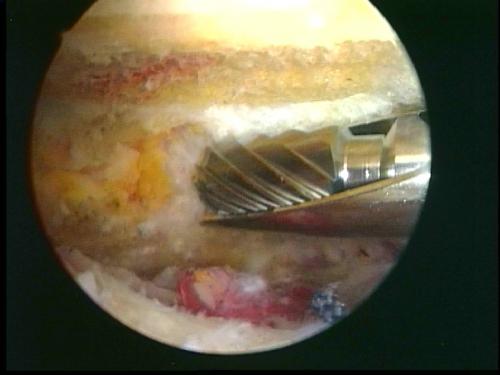

Поврежденные структуры восстанавливаются с использованием наиболее современных методик. К повреждениям, которые можно восстановить артроскопически, относятся: нестабильность, повреждения длинной головки двуглавой мышцы, адгезивный капсулит. Вторая часть операции производится в пространстве над головкой плечевой кости – в подакромиальном пространстве. Здесь находится причина хронического бурсита и повреждений сухожилий вращательной манжеты. После обработки хронического бурсита взгляду хирурга открываются многие важные элементы плечевого сустава. Дефекты сухожилий вращательной манжеты могут быть восстановлены при помощи швов и якорных фиксаторов. Кальцификат при кальцифицирующем тендините обнажается после обработки хронического бурсита и может быть легко удалён. Последним осматривается акромиально-ключичный сустав, артроз которого может причинять значительную боль при обычных бытовых нагрузках.

Иллюстрация: декомпрессия субакромиального пространства